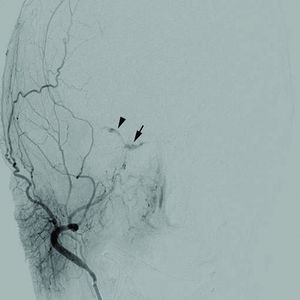

1471-2415-12-28-1Cerebral angiogram.jpg

Cerebral angiogram of a carotid-cavernous fistula

أما التشخيص فقد يعتمد على عدة إجراءات منها تصوير الدماغ (الطبقي المحوري وأحياناً المرنان المغنطيسي) أو إجراء بزل قطني لتحري وجود الدم في السائل الدماغي الشوكي. ومن الإجراءات المهمة تصوير الشرايين الدماغية (بوساطة القثطرة) للتحري عن وجود تشوهات وعائية.

ـ معالجة التشوه الوعائي في حال وجوده: وذلك بالجراحة أو بوساطة القثطرة الشريانية في بعض الحالات (يتم ملء أم الدم بمواد خاصة تؤدي إلى توقف جريان الدم ضمنها وبالتالي الحيلولة دون توسعها ونزيفها مجدداً).